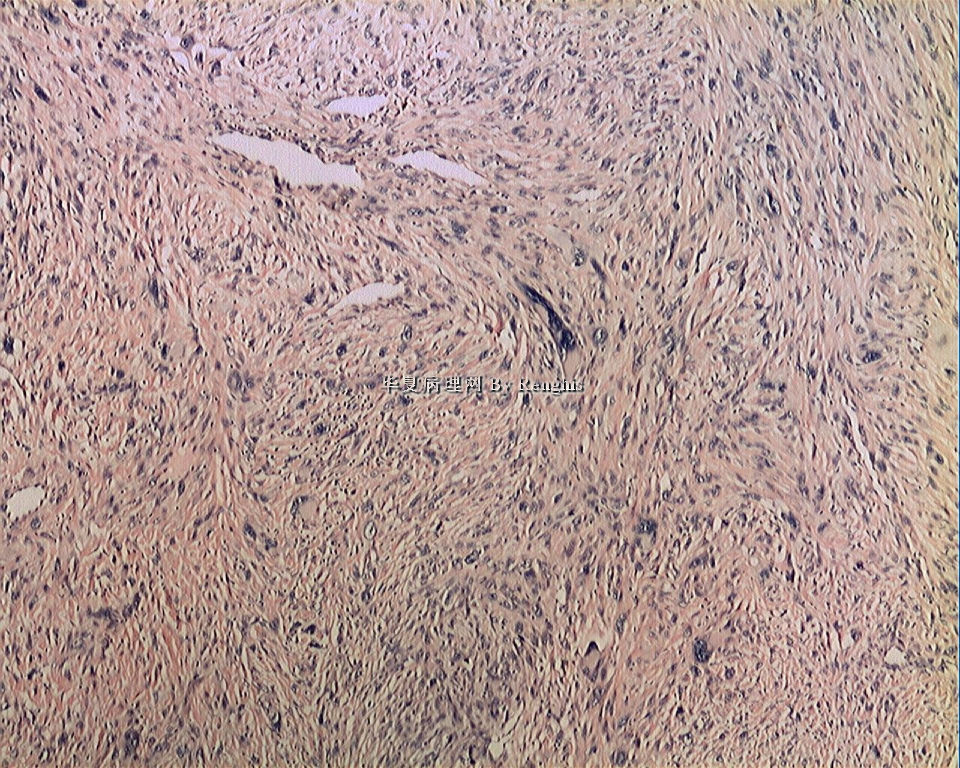

女,29岁,左大腿内侧肿物直径2.8cm,切面灰白、实性、质中,似有包膜。

本人认同此例是一例比较典型的纤维肉瘤,瘤细胞程束状、鱼骨状及编织状排列,部分瘤细胞异型性明显,免疫组化vimentin阳性,SMA灶状弱阳性,desmin阴性,S100阴性,CK阴性,EMA阴性,余记不得了,明天看看再上传。